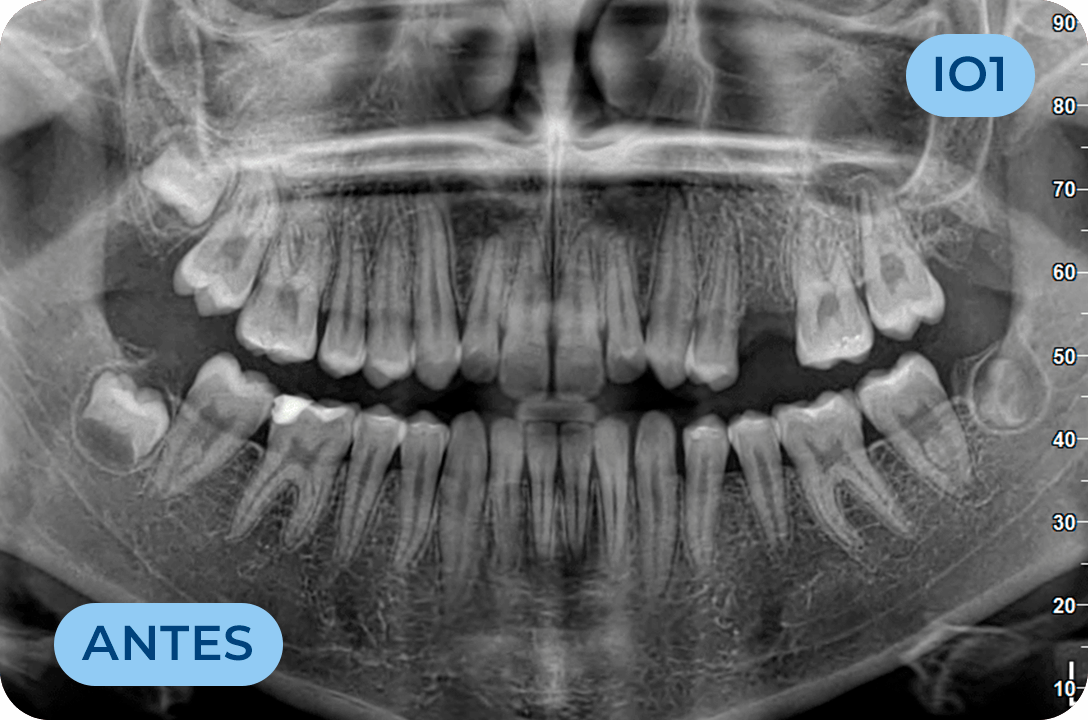

Implantologia Oral

É a área clínica que permite substituir os dentes ausentes através da colocação de implantes dentários. É uma solução definitiva, fixa e estética, que permite substituir apenas um dente, vários dentes ou todos os dentes.

Periodontologia

Especialidade da Medicina Dentária que trata das doenças que afetam as gengivas que suportam os dentes. É responsável pelo tratamento da doença que leva à perda do maior numero de dentes em todo o mundo, a periodontite.

Cirurgia Oral

Área da medicina dentaria que diagnostica e trata as lesões e anomalias dos dentes, tecidos moles e estruturas anexas aos maxilares. A extração de dentes irrecuperáveis, dentes inclusos, supranumerários, frenectomias (eliminação dos freios), biopsias, exérese de quistos e outras lesões dos tecidos orais, fazem parte do seu vasto campo de execução.